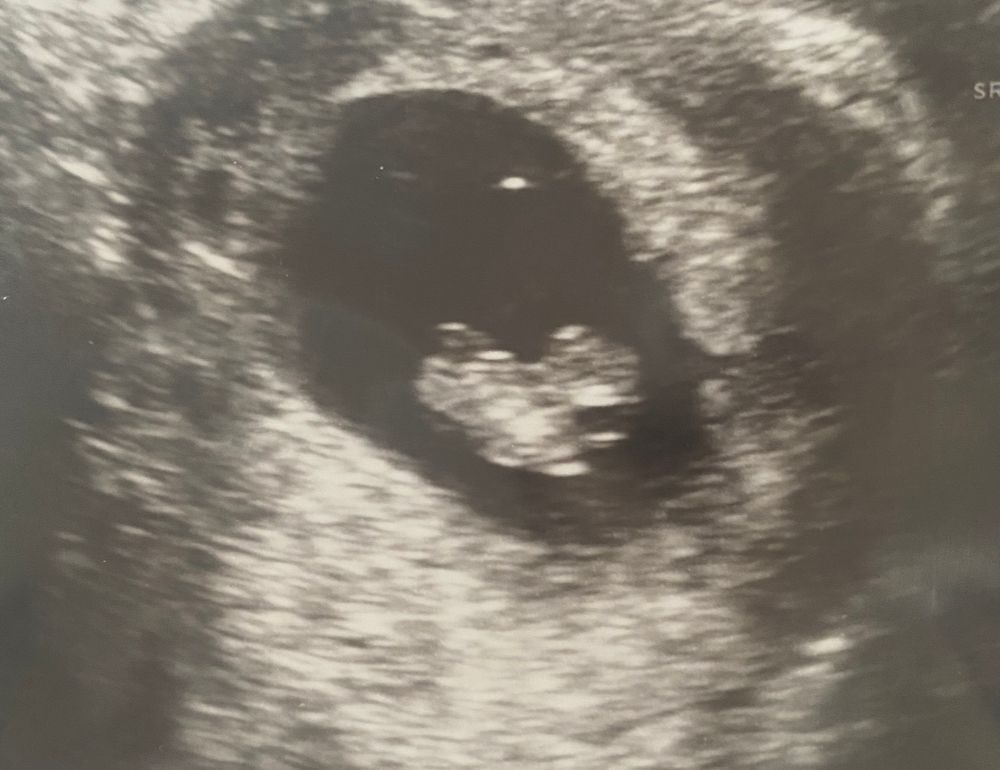

Плодное яйцо 22,8, а ктр 21,3 мм 😬

Девочки, привет 👋 Сегодня была на узи в итоге крошка так лежит в пя, что если она будет расти то упрется в стенки плодного яйца. Пя овальной формы и крошка по узкому месту расположена. Может ли он развернуться?

Не переживайте. По фото я не вижу,что вашей ляле мало места,но мониторьте картину! Рост пя очень важен..говорю на своем опыте..все будет хорошо🙏

Знаете, я конечно не эксперт, но вот по фото вообще не похоже, что ему там тесно, к тому же плодное яйцо ведь тоже растёт.